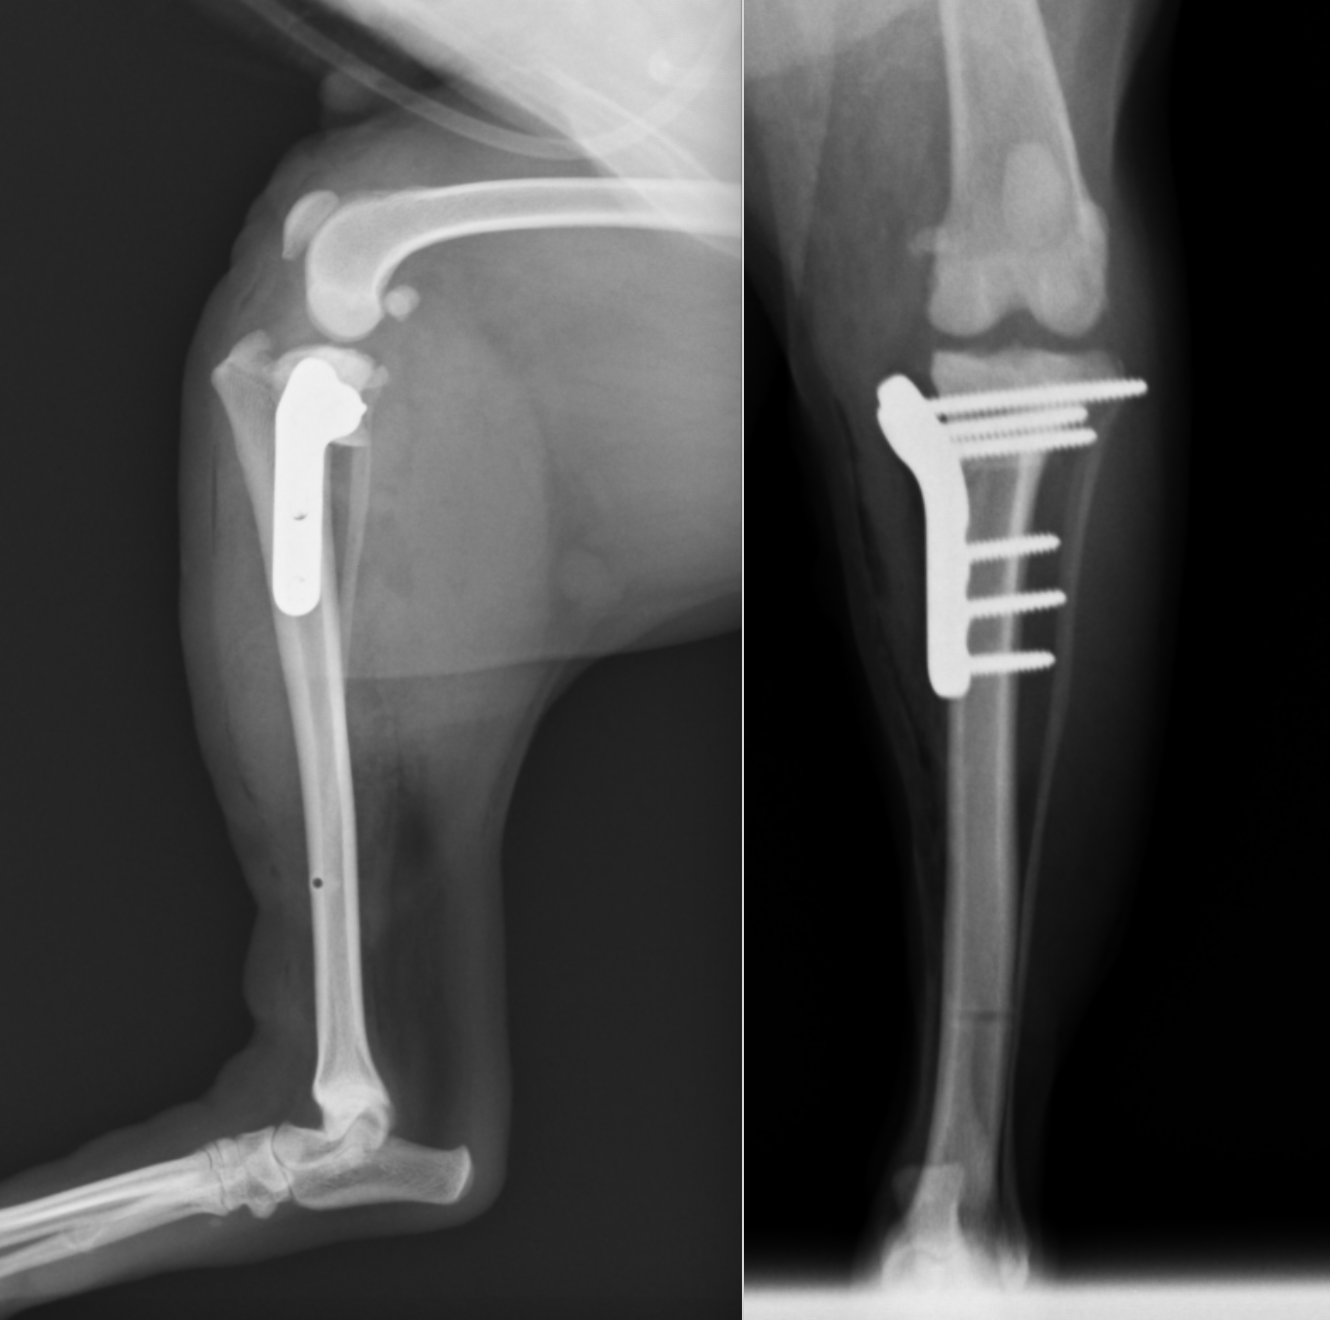

近年では小型犬の前十字靭帯断裂も増えてきています。背景には膝蓋骨内方脱臼によるものが関与していると考えられます。このレントゲンも4kgほどのトイプードルです。

カーブプレートというプレートを用いています。前方の圧迫もかけられる新しいタイプのプレートです。

こちらもカーブプレートです。

2kg代の子にはFixinというプレートを用いることもあります。